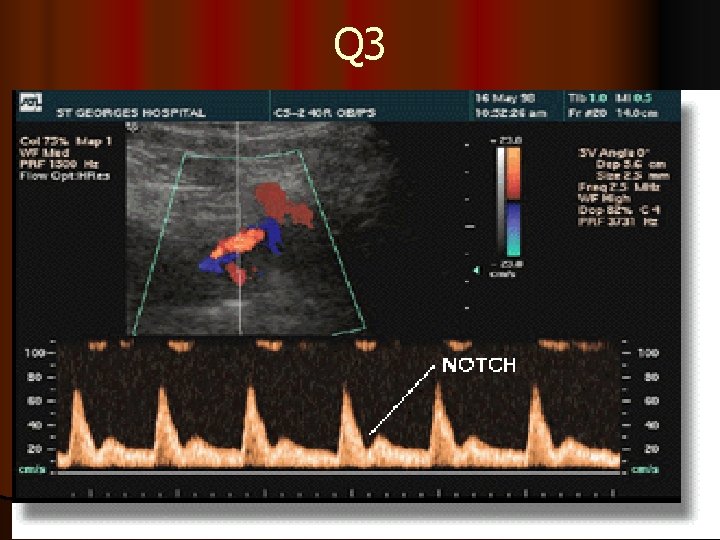

Q 4

The resistance index (RI) is the most commonly used index to measure the uterine artery flow as it is unlikely to have absent or reverse end Diastolic (EDF) flow. Although the pulsatility index (PI) can also be used 3. High resistance waveforms in the uterine artery with early diastolic notching in the second trimester are asssociated with the later development of preeclampsia, IUGR, placental abruption and intrauterine death. 4. notches of the uterine artery waveform with a high RI, hold the most risk of complicated pregnancies, although it is still to be established wether the notch or the high RI is the best indicator of poor outcome 5. Systole (Sys) and diastole (D) are identified in green Note that diastole is less at 20 weeks (yellow ellipse) than at 36 weeks (red ellipse). 6. This illustrates absent diastolic flow during diastole. When this occurs there is abnormal resistance in the placenta which results in a marked decrease in blood flow from the fetus to the placenta.